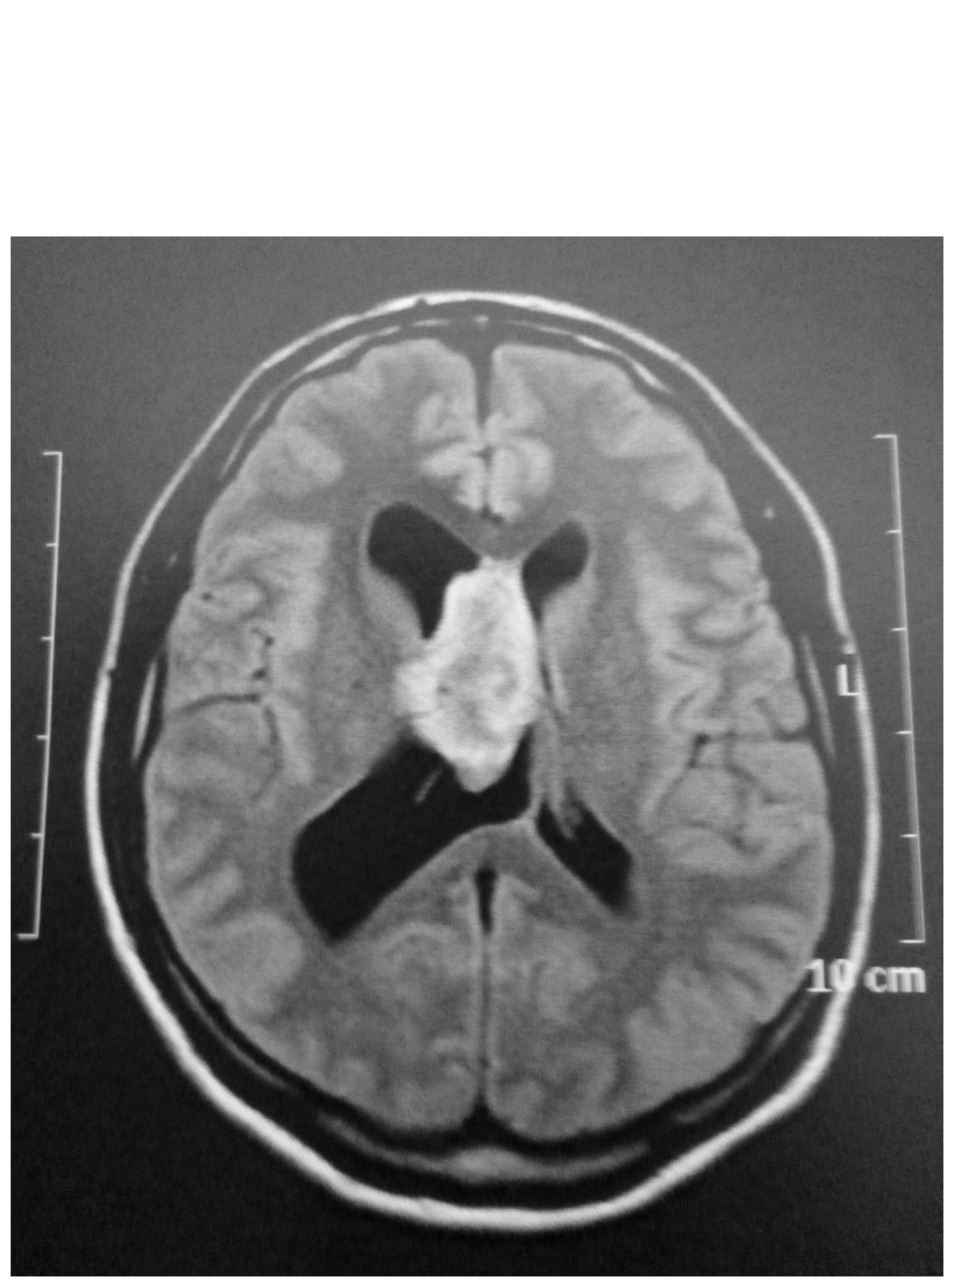

Quel est votre diagnostic ? Hémorragie intraventriuclaire Toxoplasmose cérébrale Tumeur du plexus choroïde Neurosarcoïdose Histiocytose OK Il s'agit d'une tumeur du plexus choroïde. Valider mes réponses

Il s'agit d'une tumeur du plexus choroïde.